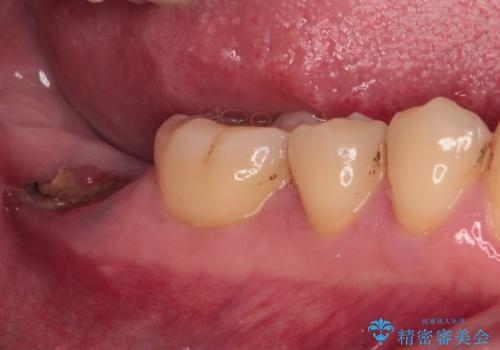

- 左下欠損部のインプラント治療を希望して来院された患者様です。

左下の欠損部を長期間欠損を放置していたことで、咬み合う上の奥歯が動いてしまっていたので、まずは上顎奥歯の部分矯正を行うこととしました。

理想的な咬み合わせに改善した上で、インプラント補綴治療を行うこととしました。